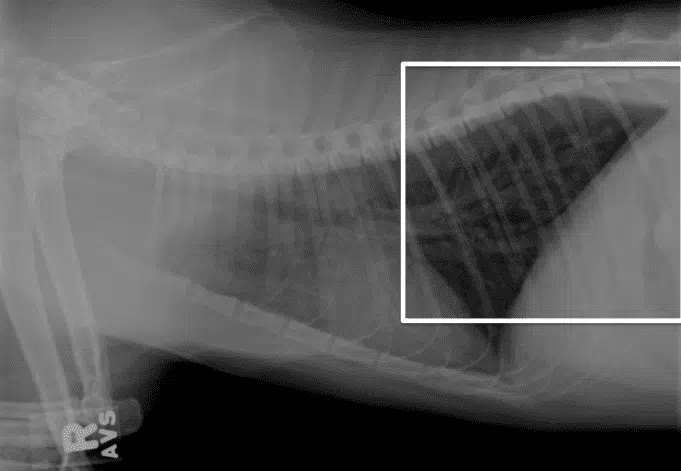

Preguna 3 - Multiple respuesta

- Se observa un rotacion artefactual del mediastino

- El mediastino está rotado por una enfermedad pleural.

- Hay signos de neumotorax

No hay efusion pleural porque se ve aire, no liquido. No suelen preguntar patrones bronquiales (Esto se verá a nivel radiográfico estructuras circulares con pared radiopaca como “Donuts y líneas radiopacas paralelas como “railes de tren”, en función de si la imagen lo ha cortado de forma transversal o longitudinal, respectivamente.)